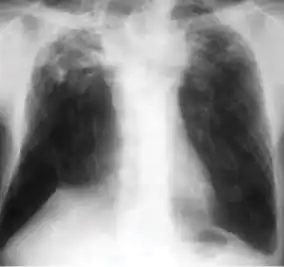

Chest x-ray showing patchy opacification on the upper right and mid-zone lung with fibrotic shadows, as well as bilateral hilar lymphadenopathy. -